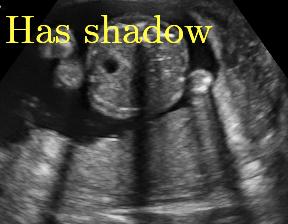

We propose a novel method based on convolutional neural networks (CNNs) to automatically estimate pixel-wise confidence maps of acoustic shadows in 2D US images. Our method learns an initial latent space of shadow regions from images consisting of multiple anatomies and with global image-level labels (“has shadow” and “shadow-free”), e.g. Fig. 1(a). The basic latent space is then estimated by learning from fewer images of a single anatomy (fetal brain) with coarse pixel-wise shadow annotations (approximately of the images with global image-level labels), e.g. Fig. 1(b). The resulting latent space is then refined by learning shadow intensity distributions using fetal brain images so that the latent space is suitable for confidence estimation of shadow regions. By using shadow intensity information, our method can detect more shadow regions than the coarse manual segmentation, especially relatively weak shadow regions.

We propose a shadow-seg module to extract generalized shadow features for a large range of shadow types in fetal US images under limited weak manual annotations. Since shadow regions have different shapes, various intensity distributions and uncertain edges, the pixel-wise annotation of shadow regions is time consuming and relies heavily on annotator’s experience (e.g. various annotations in Fig. 1(b)). This generally results in manual annotations of limited quantity and quality. Compared with pixel-wise shadow annotations, global image-level labels (“has shadow” and “shadow-free” in our case) are easier to obtain, and shadow images with global image-level labels can contain a larger variety of shadow types. Therefore, we use a shadow-seg module that combines unreliable pixel-wise annotations and global image-level labels as weak annotations.The proposed shadow-seg module contains two tasks, (1) shadow/shadow-free classification using image-level labels, and (2) shadow segmentation that uses few coarse pixel-wise manual annotations ( of the global image-level labels). Shadow features can be extracted during simple shadow/shadow-free classification and subsequently optimized for the more challenging shadow segmentation task. In our case, shadow features extracted by the classification network cover various shadow types in a range of anatomical structures. These shadow features become suitable for the shadow segmentation after being optimized by a shadow segmentation network.